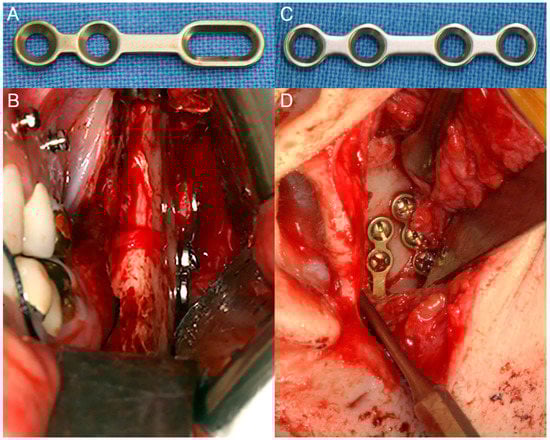

2.2. Surgical Procedures